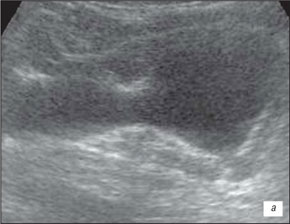

Ехограма нирки

а – запальні зміни в нирці;

б – втягнення на контурі нирки (стрілка)

На данній ехограмі ми помічаємо чіткий патологічний осередок ураження сечоводів, їх розмірів і глибину залягання.